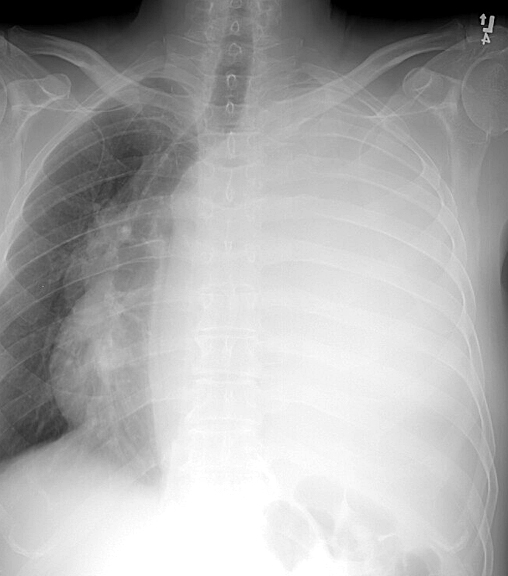

Gallery Pleural huge effusion PA

huge effusion PA